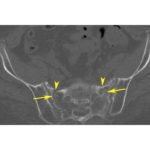

Insufficiency Fractures of the Skeleton

Courtesy: Shantaram Shetty, Ashok Shyam, IORG, OrthoTV